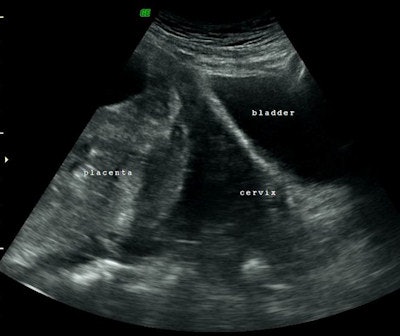

Over the last two years, 12 women (ages 28-46) who urgently needed uterine arteries ballooning and embolization to prevent and control bleeding after a C-section were referred to the interventional radiology service at Al Ain Hospital. Seven of these women were diagnosed with invasive placenta that was confirmed by a predelivery MRI. Interventional radiologists worked in a multidisciplinary team with obstetricians. The interventional radiologists guided balloon catheters into a woman's left and right uterine artery (preoperative prophylactic insertion of bilateral internal iliac artery occlusion balloons) before delivery -- to be ready to inflate (just like in angioplasty), if needed at delivery to block excessive blood flow.

After delivery, if an invasive placenta could not be delivered, the obstetrician left the placenta in place; interventional radiologists used uterine artery embolization -- with absorbable gelatin sponge -- to close blood vessels to the placenta, in essence, cutting off its blood supply so that it would die and eventually be reabsorbed by the body.

Often these women are scared; this is a very serious and dangerous condition. Before interventional radiology treatment was available, the placenta couldn't be delivered and women would need a hysterectomy, or in some cases died. At our hospital, interventional radiologists control excessive bleeding in women with a combination of balloon catheters inserted into uterine arteries predelivery (that could be inflated to control bleeding, if necessary), and uterine artery embolization after delivery (if the placenta could not be delivered).